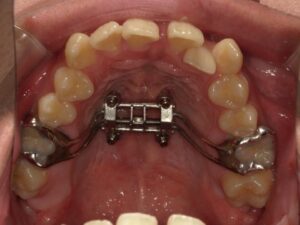

MSEとは、上顎を広げるための装置です。

正式には「Maxillary Skeletal Expander)」といいます。

・真ん中にネジ(スクリュー)があり、それを回すことで拡大力を発生させます。

・装置の基部がミニスクリュー(4本程度)で上顎骨(口蓋骨)に直接固定されます。

・骨に固定するため、歯の傾斜を抑えて上顎骨そのものを広げることができます。